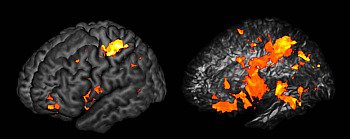

The researchers found that, rather than residing in a single structure, general intelligence is determined by a network of regions across both sides of the brain.

"One of the main findings that really struck us was that there was a distributed system here. Several brain regions, and the connections between them, were what was most important to general intelligence," explains Gläscher.

"It might have turned out that general intelligence doesn't depend on specific brain areas at all, and just has to do with how the whole brain functions," adds Adolphs. "But that's not what we found. In fact, the particular regions and connections we found are quite in line with an existing theory about intelligence called the 'parieto-frontal integration theory.' It says that general intelligence depends on the brain's ability to integrate—to pull together—several different kinds of processing, such as working memory."

The brain regions important for general intelligence are found in several specific places (orange regions shown on the brain on the left). Looking inside the brain reveals the connections between these regions, which are particularly important to general intelligence. In the image on the right, the brain has been made partly transparent. The big orange regions in the right image are connections (like cables) that connect the specific brain regions in the image on the left.